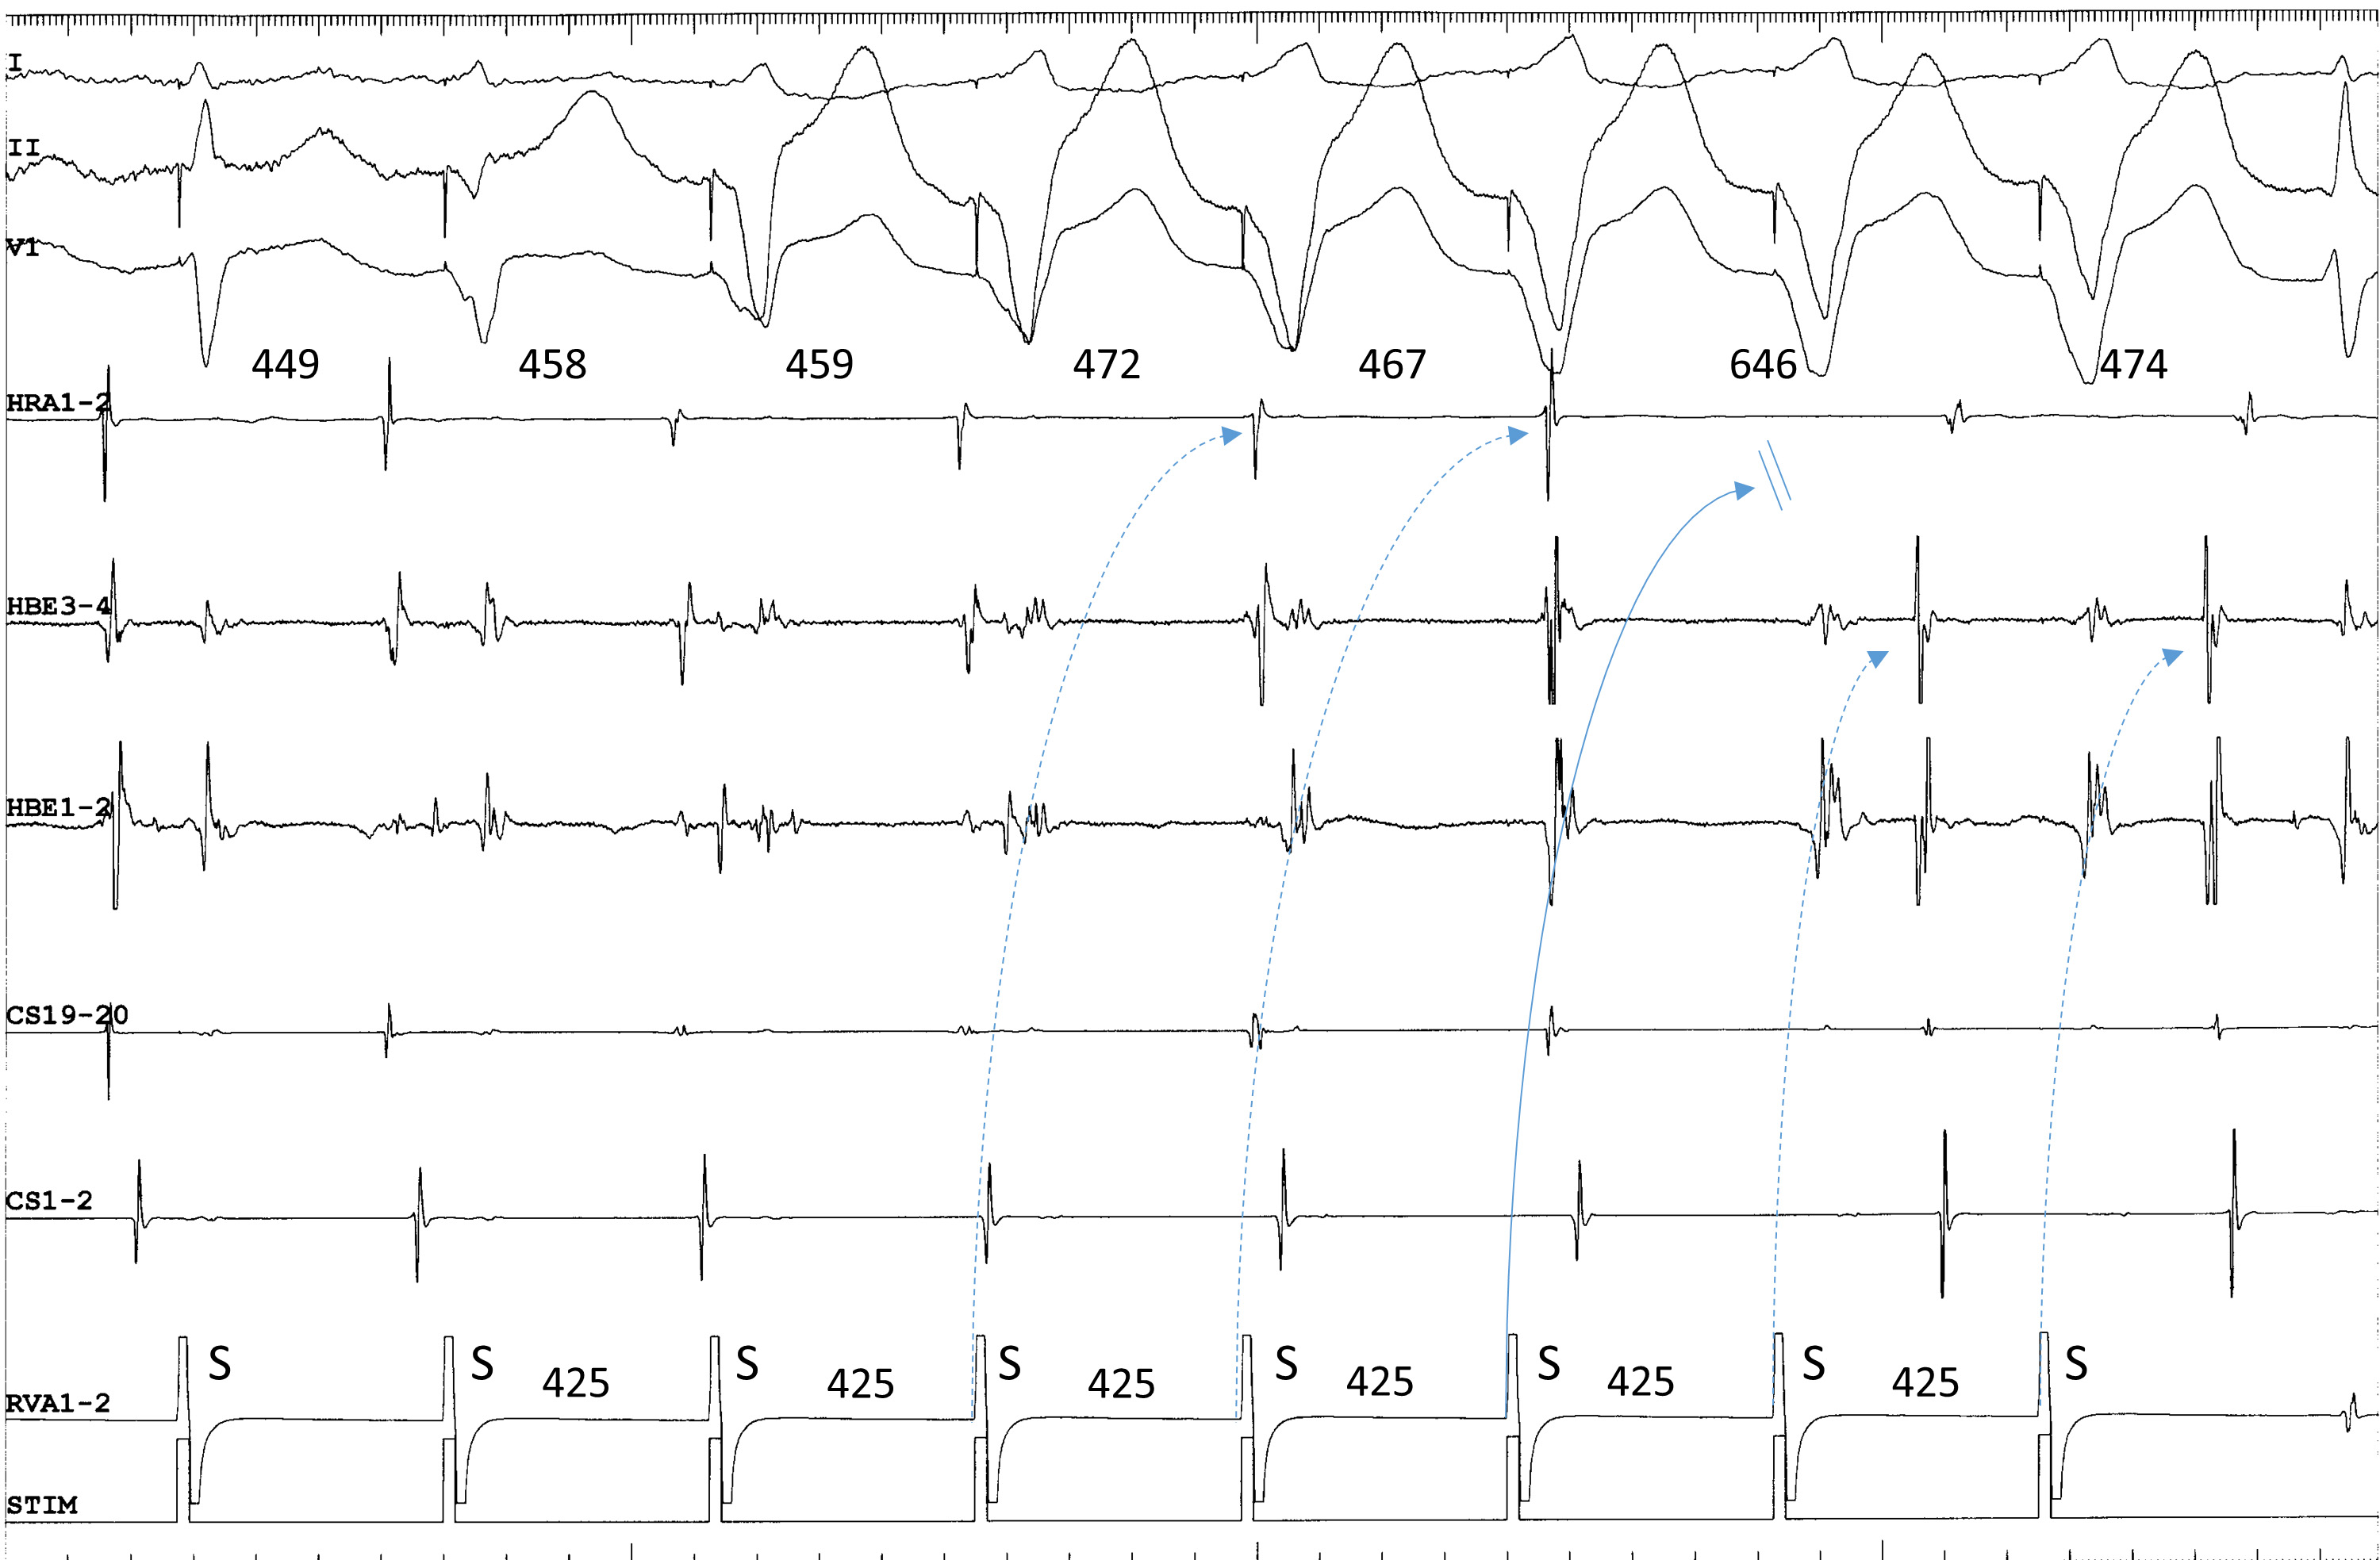

Third, when the tachycardia is terminated by ventricular overdrive pacing, the atrial cycles immediately before the termination may lengthen transiently, due to repetitive retrograde conduction with a decremental delay over the superior SP, followed by orthodromic block inside the superior SP (Fig. 2). This is not simple ventricular entrainment nor termination without atrial capture, but a frequently observed, confirmatory, diagnostic phenomenon which excludes the diagnosis of atrial tachycardia.

Fig. 2.Termination of fast-slow AVNRT using a superoanterior SP during

ventricular overdrive pacing at an S-S cycle length of 425 ms from the right

ventricular apex (RVA1-2). The site of earliest atrial activation during

tachycardia is recorded in the HRA (HRA1-2). The atrial cycle length immediately

after the 4th and 5th stimuli lengthens slightly without change in the atrial

activation sequence, consistent with an orthodromic capture of the atria over the

superoanterior SP, with a decremental delay in response to the 4th and 5th

stimuli (dotted arrows). The 6th stimulus is blocked (straight arrow), evidenced

by the absence of retrograde activation over the SP in its wake. In response to

the 6th and 7th ventricular stimuli, the site of earliest retrograde atrial

activation was observed in the distal electrogram of the His bundle region

(HBE1-2) along with a short ventriculoatrial interval, consistent with retrograde

conduction over a FP. The numbers above the HRA1-2 channel are the interatrial

intervals. I, II and V